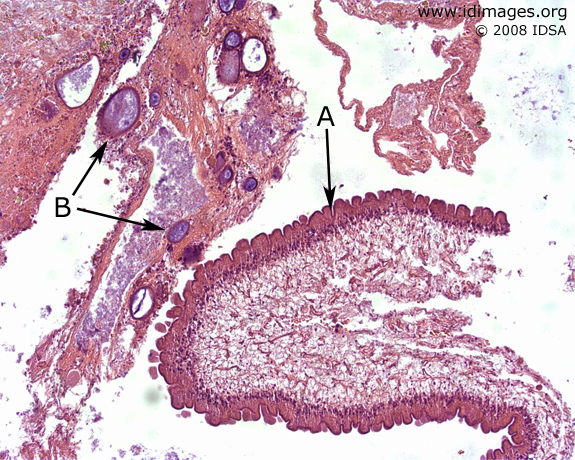

Taenia solium

Figure 1.

shown by hematoxylin and eosin stain of resected thecal cyst, with cyst wall A and mineralized calcareous bodies B.

Spine

Photomicrography

Hematoxylin and Eosin Stain